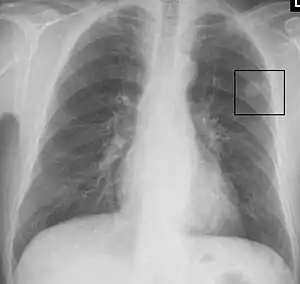

Cancer is a group of diseases involving abnormal cell growth with the potential to invade or spread to other parts of the body.[2][8] These contrast with benign tumors, which do not spread.[8] Possible signs and symptoms include a lump, abnormal bleeding, prolonged cough, unexplained weight loss, and a change in bowel movements.[1] While these symptoms may indicate cancer, they can also have other causes.[1] Over 100 types of cancers affect humans.[8]